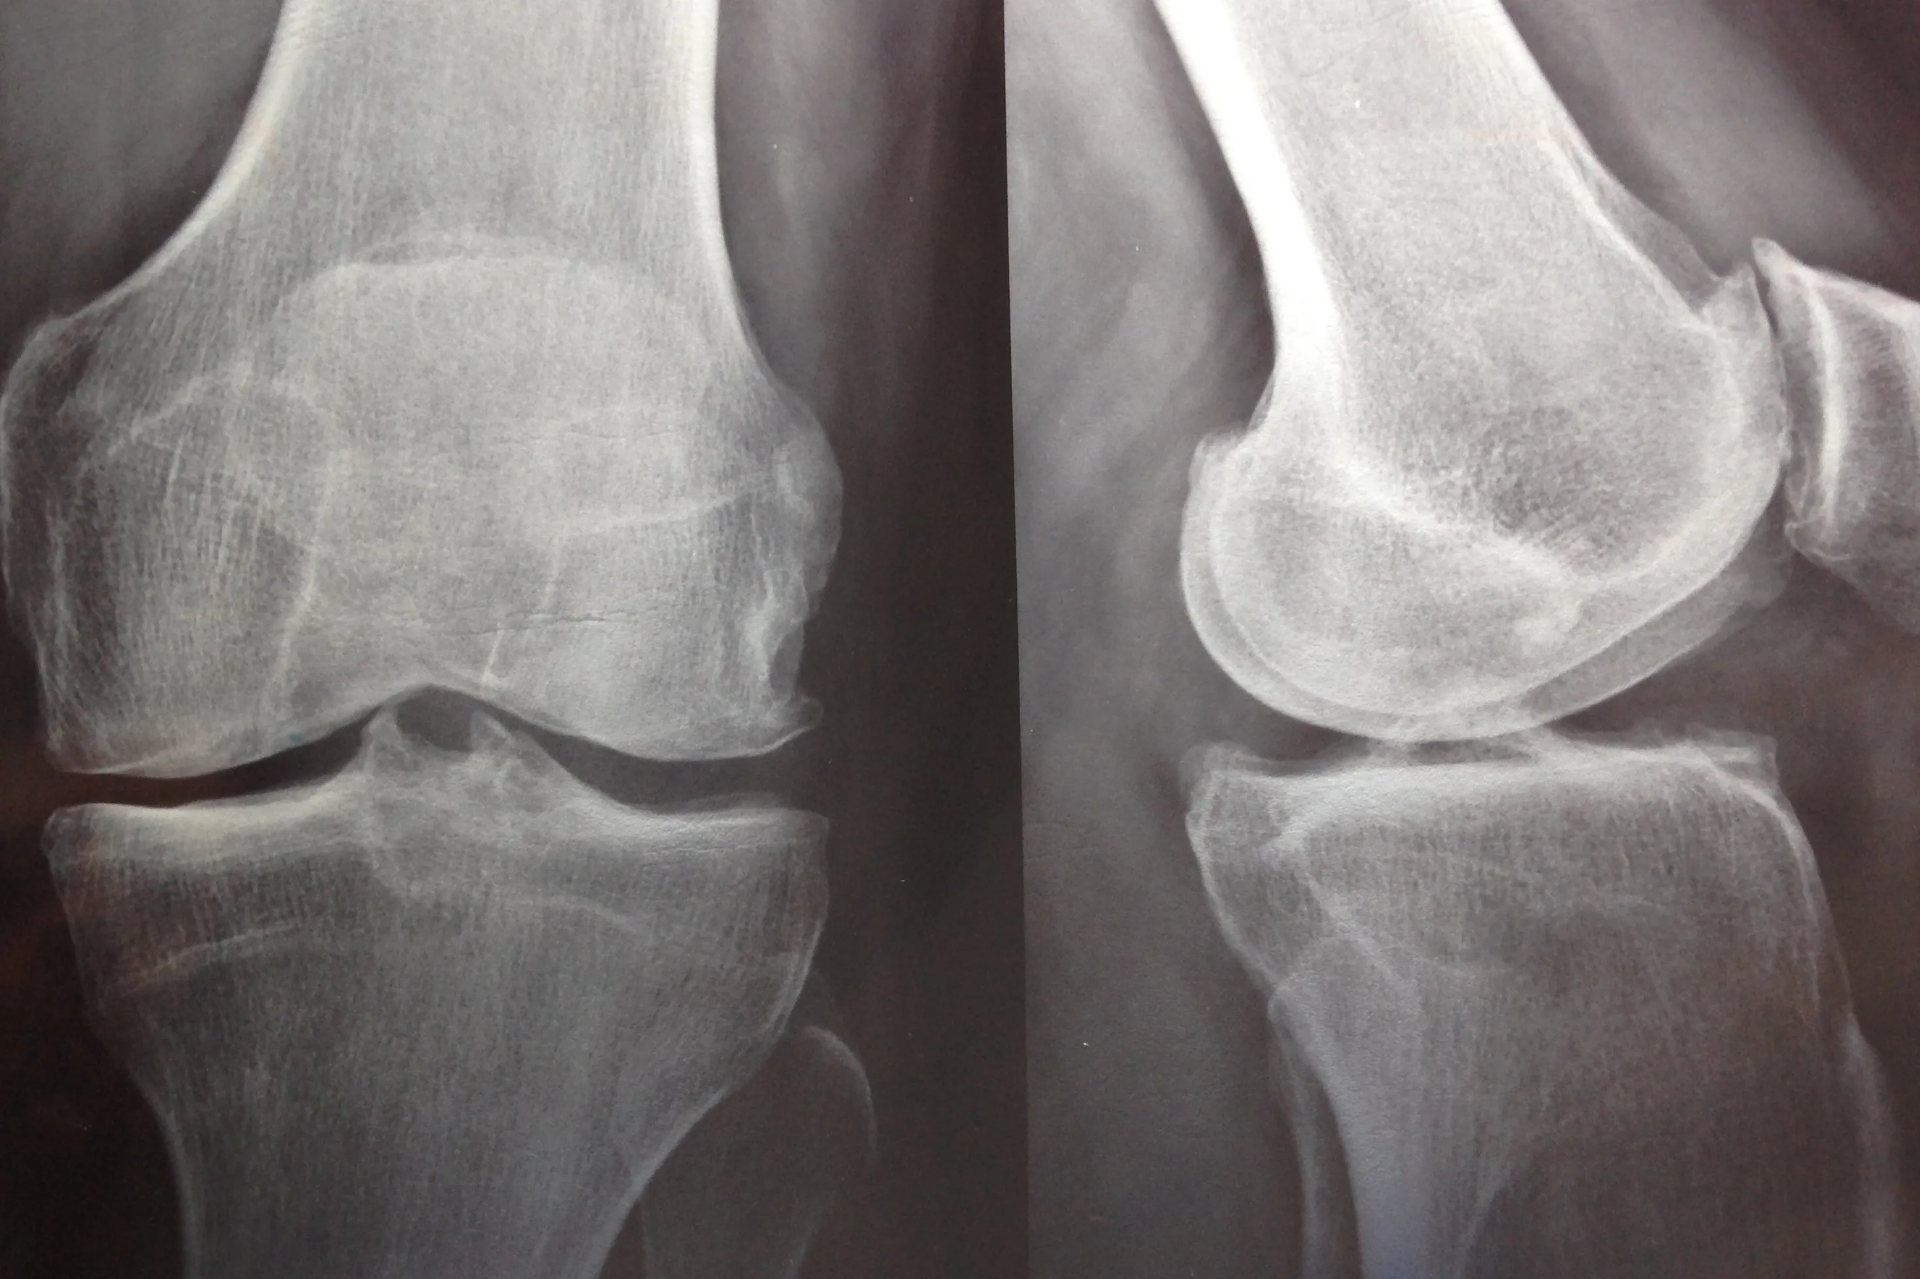

Resumen Visual de Artrosis de rodilla

Imagen resumen sobre Artrosis de rodilla